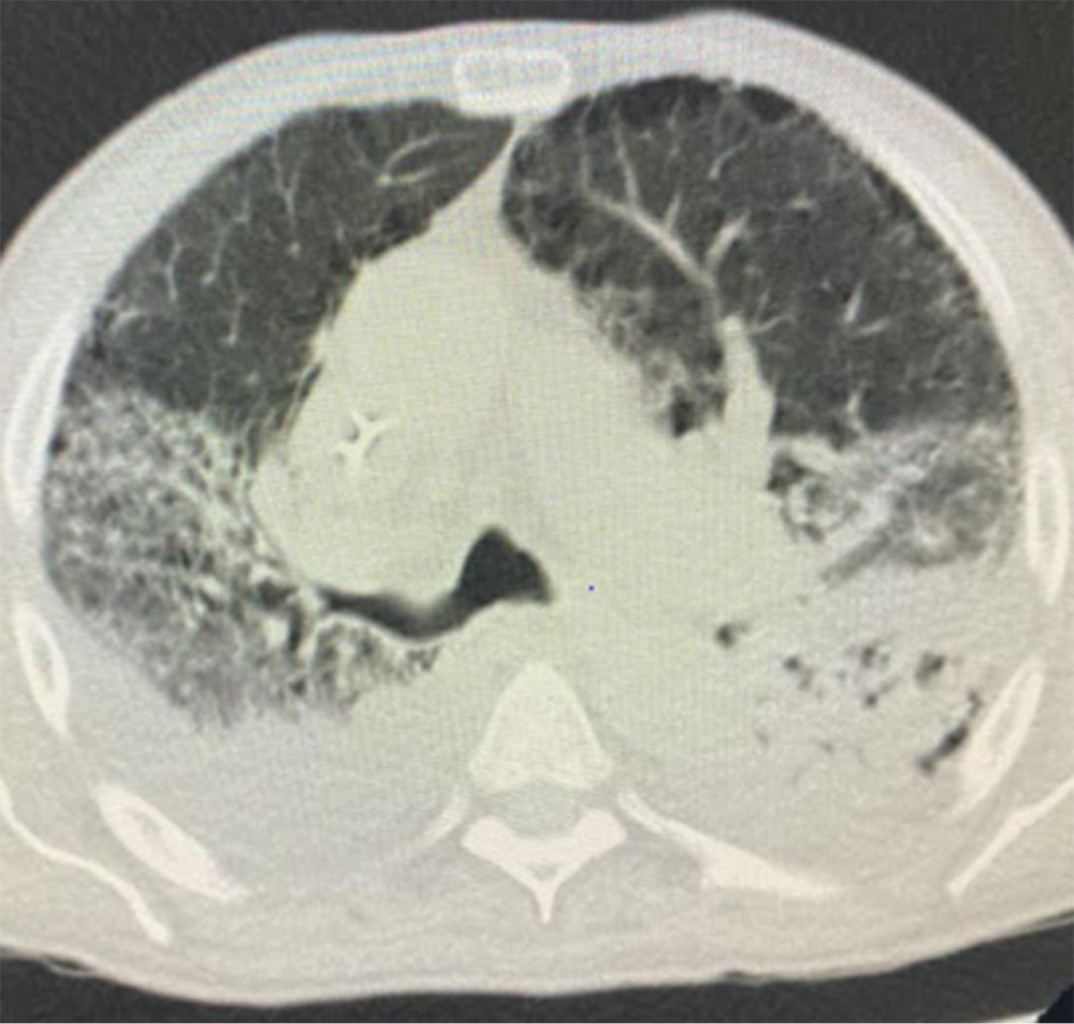

Figure 4